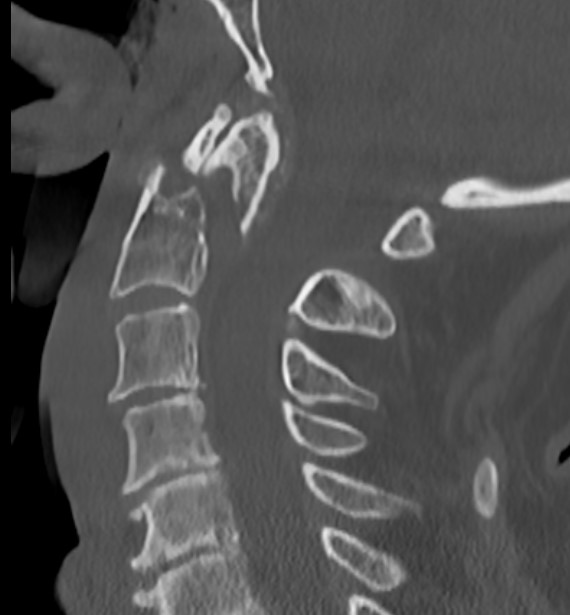

Type 2

Fracture of base of odontoid process

- most common type

- > 50%

Type II Dens Fracture

Issue

Stability

Union

Elderly

Non-union

Vascular watershed area

- at base of odontoid

- increases risk of nonunion

Risk factors for nonunion

- 69 patients with acute type II fractures treated with halo vest

- union 32/69 (46%)

- nonunion associated with:

- fracture gap > 1 mm

- posterior displacement > 5 mm

- delay in treatment > 4 days